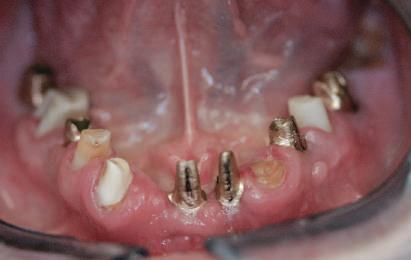

Refrezarea bonturilor individualizate

Pacientul prezenta dentiţie maxilară şi mandibulară eşuată datorită cariei secundare provocată de xerostomia post-iradiere. Pacientul suferise o disecţie cervicală radicală pentru înlăturarea carcinomului cu celule scuamoase la nivelul gâtului cu 9 ani înainte, urmată de radioterapie dar fără limită de ecranare. S-a utilizat o abordare stadializată pentru a evita protezele mobilizabile pe ţesuturile moi, extrem de uscate. Pacientul a optat pentru tratarea prioritară la nivel mandibular.

Fig. 9 prezintă bonturile de vindecare adiacente dinţilor naturali menţinuţi temporar, iar fig. 10 bonturile individualizate din prima etapă, inserate cu un contur gingival relativ bun şi fără recesie. Recesia era clar vizibilă în jurul tuturor bonturilor din prima etapă, după extracţiile adiacente şi plasarea implanturilor din a doua etapă (fig. 11). Atitudine: S-a decis îndepărtarea acestor bonturi şi amprenta corpului implantar al tuturor implanturilor astfel încât bonturile noi şi cele din prima etapă să fie frezate împreună pentru paralelism şi poziţionarea adecvată a marginii gingivale. Întrucât aceasta necesita îndepărtarea bonturilor din prima etapă care menţineau proteza provizorie, înainte de îndepărtarea tuturor bonturilor individualizate s-au plasat bonturi provizorii, cu scopul de a asigura poziţionarea adecvată şi dimensiunea verticală a restaurării provizorii. Aceste bonturi provizorii au menţinut apoi restaurarea temporară,

Cazul (3): Refrezarea bonturilor individualizate

Figurile

9. Bonturile de vindecare.

10. Bonturile individualizate în prima etapă.

11. Recesia evidentă în jurul bonturilor din prima etapă, după extracţiile adiacente şi inserarea implanturilor din faza a doua.

12. Bonturile refrezate şi noile bonturi individualizate.

în timp ce toate bonturile individualizate au fost fabricate şi/sau frezate în laborator. Fig. 12 prezintă plasarea bonturilor refrezate (la implanturile din prima etapă) şi bonturile individualizate noi (la cele din a doua etapă).